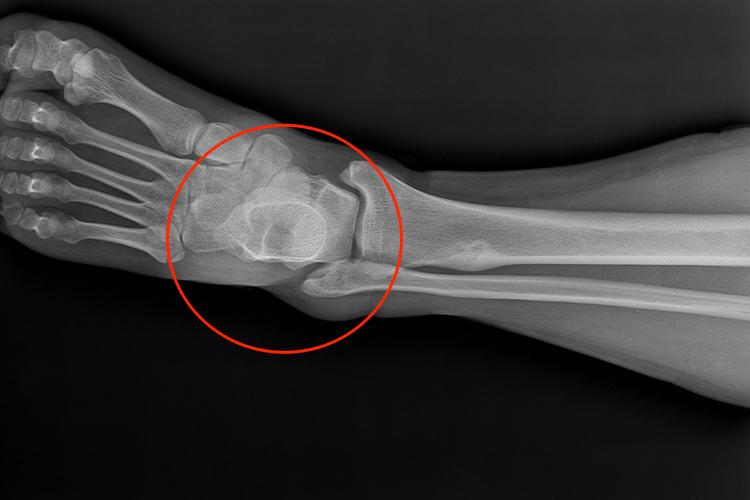

软骨瘤

发生于指(趾)骨的软骨瘤,通常位于骨中央。软骨瘤X线征象表现为边缘清晰、整齐的椭圆形囊状透明阴影,呈膨胀性生长,受累骨皮质因膨胀变薄,周围会有一薄层增生硬化现象,在透明的肿瘤阴影内,可见散在的砂粒样钙化点,有些表现为模糊的烟圈样钙化,这是主要X线特征。